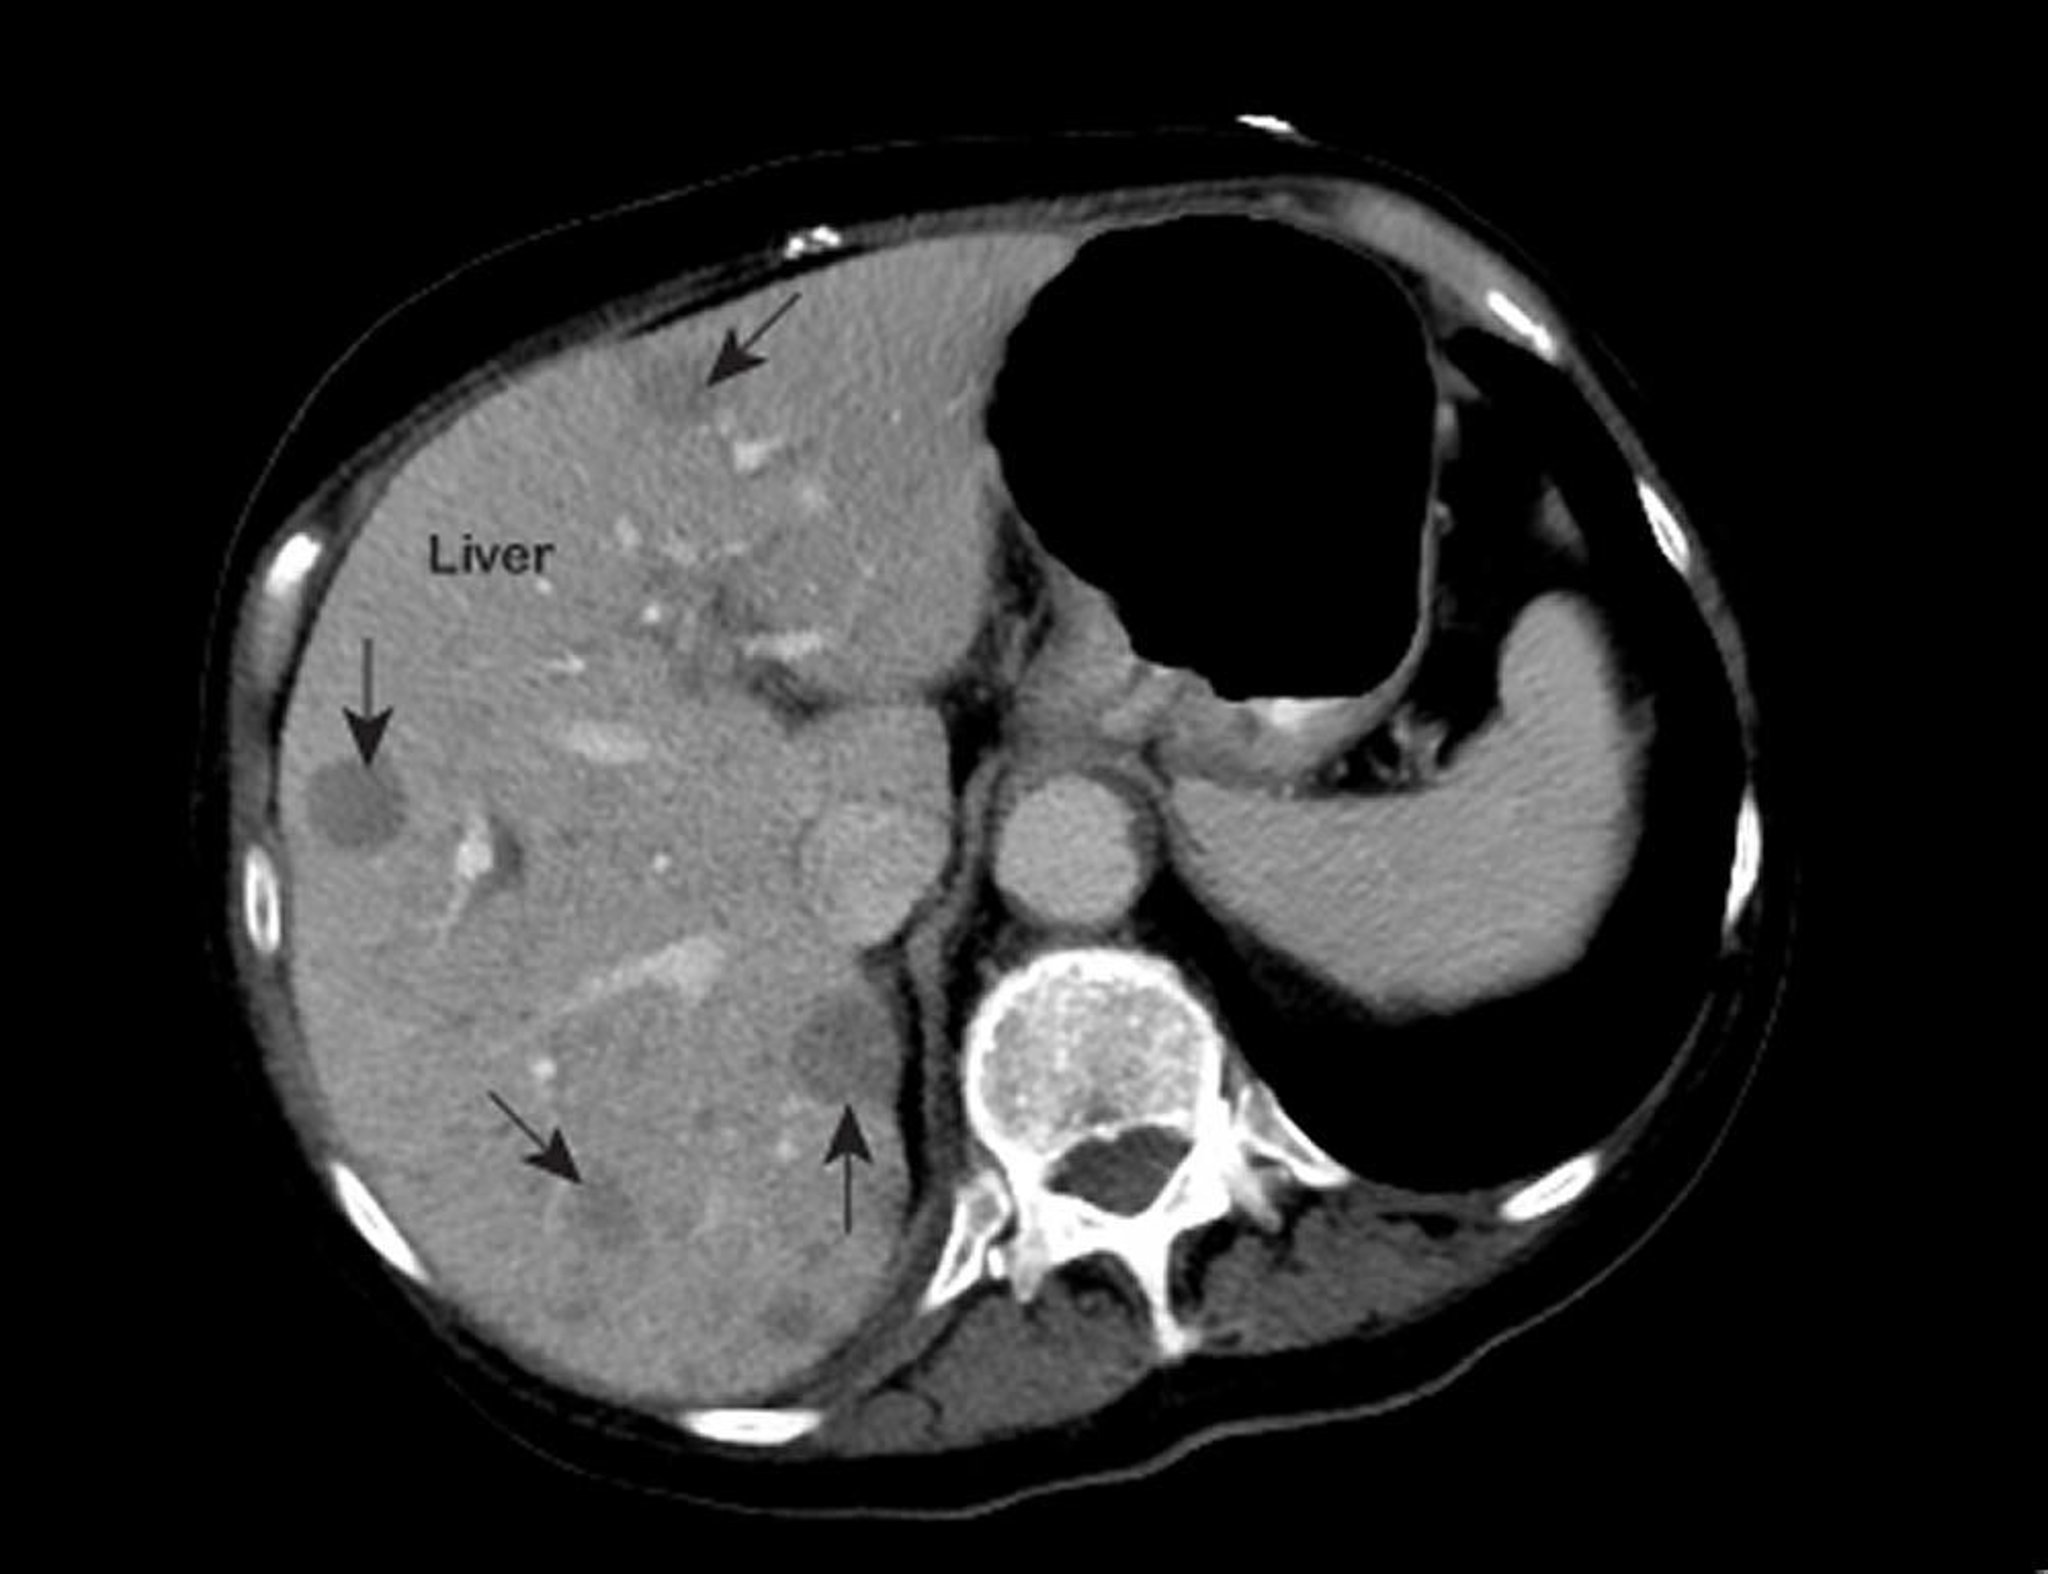

मेटास्टेटिक लिवर कैंसर

सीने के असामान्य मैग्नेटिक रीसोनेंस इमेज (MRI) से लिवर के अंदर असामान्य हिस्सों को दिखाया जाता है (जिन्हें तीर से चिंहित किया गया है)। ये निष्कर्ष मेटास्टेटिक लिवर कैंसर में विशिष्ट रूप से देखने को मिलती हैं।

पैट्रिक ओ’केन, एमडी के सौहार्द से प्राप्त फ़ोटो।